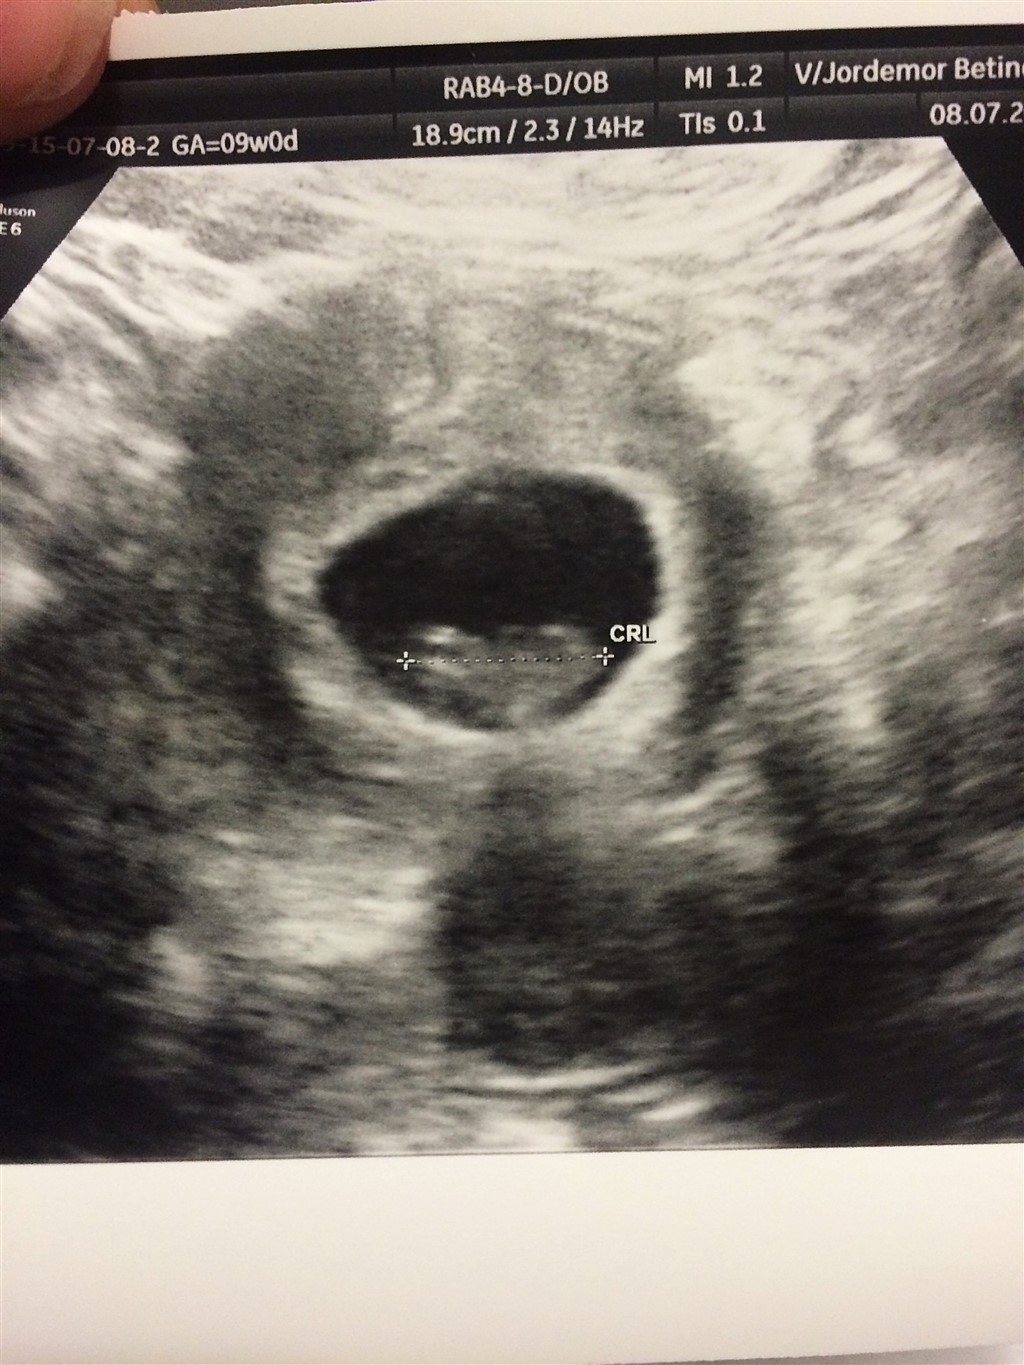

Skal i alle have afvide hvad der gemmer sig derinde?? Altså kønnet? Jeg har bestilt Kønsscanning d. 13 august

vi har to drenge i forvejen og min mand har en søn fra tidligere. Så vi håber godt nok lidt kraftigt på en pige

men er også ganske tilfredse og lykkelige over en dreng mere